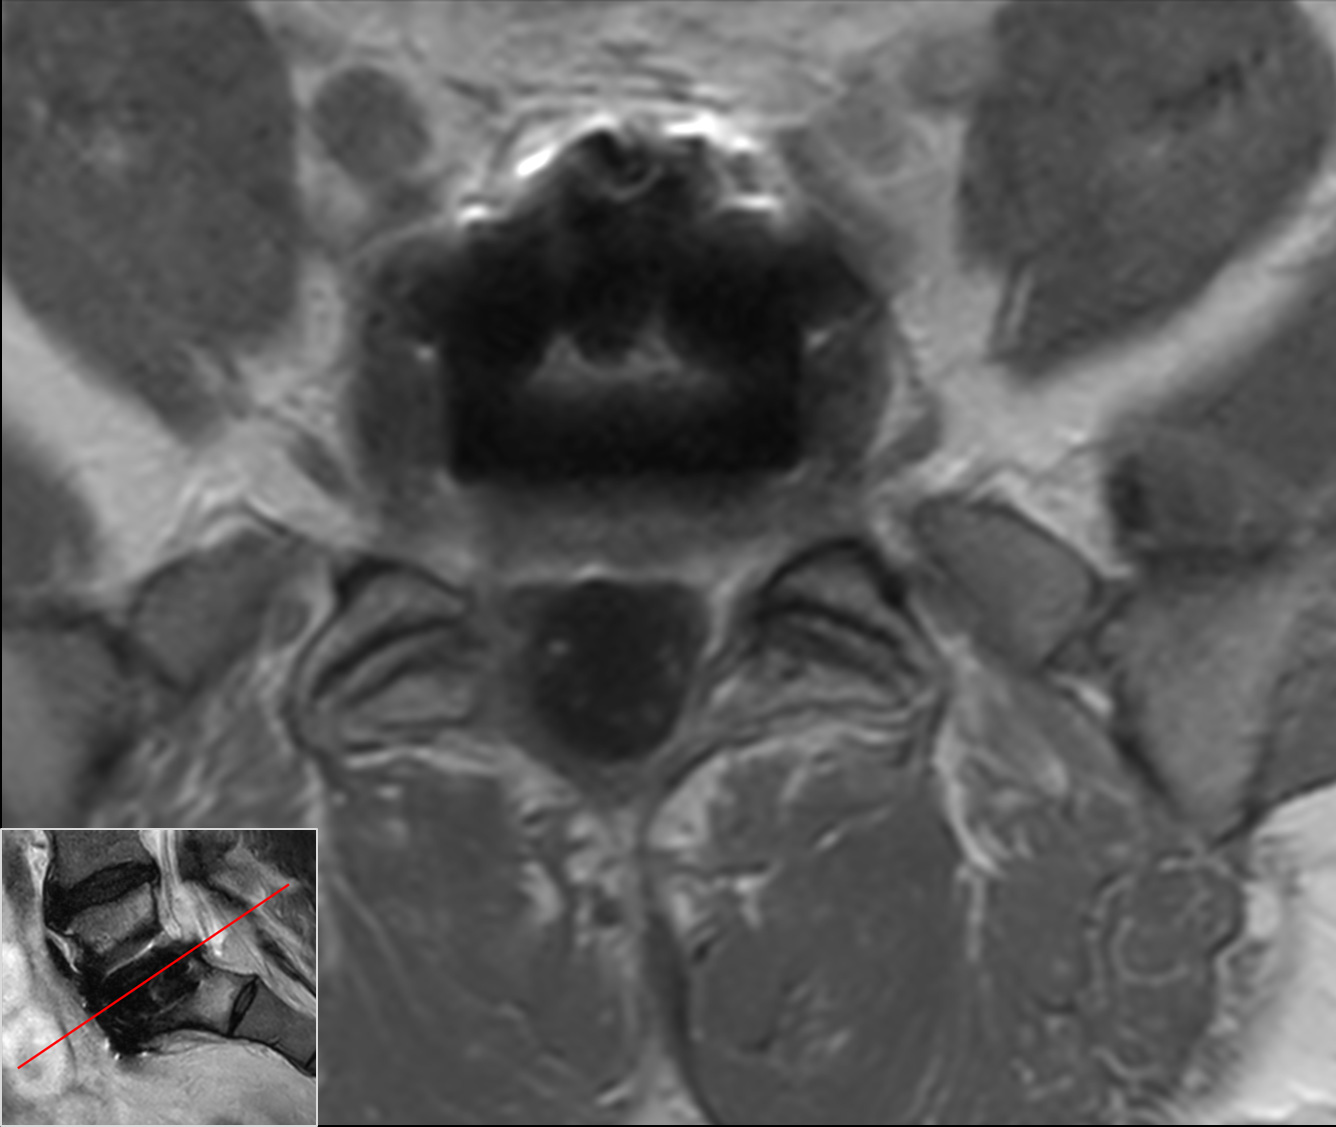

Axial T1w TSECompressed SENSE

Axial T1w TSE, post-gadoCompressed SENSE